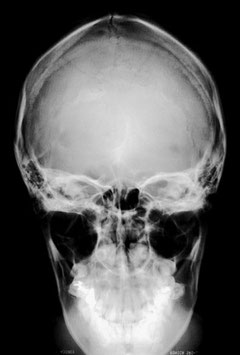

X線撮影(頭蓋骨:Skull)